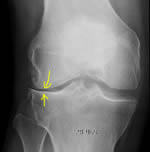

Arthrose fémoro-tibiale Externe

Petit pincement fémoro-tibial externe

Pincement complet fémoro-tibial externe